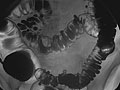

• In an air-contrast or double-contrast study, the colon is first filled with barium, and then the barium is drained out. This leaves only a thin layer of barium on the wall of the colon. The colon is then filled with air. This provides a detailed view of the inner surface of the colon. It makes it easier to see narrowed areas (strictures), diverticula, and swelling.

• Polyps or growths on the inner wall of the colon.

• Sacs in the colon wall (diverticulosis).